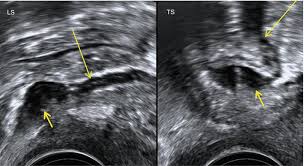

Areas of endometrial tissue found in ectopic locations are called endometrial implants. Endometriosis is a disease in which tissue resembling the inner lining of the uterus (the endometrium) starts to grow outside the uterus. The lesions are typically located in the pelvis but can occur at multiple sites including the bowel, diaphragm, and pleural cavity. Endometriosis is a disease in which tissue that is similar to the lining of the uterus grows in other places in your body. It is generally acknowledged that an estimated 10% of all women during their reproductive years (from the onset of menstruation to menopause) are. During menstrual periods it can cause severe pain, cramping, and heavy bleeding. Endometriosis is a common gynecological condition affecting an estimated 2 to 10 percent of american women of childbearing age. Endometriosis is the abnormal growth of endometrial tissue similar to that which lines the interior of the uterus, but in a location outside of the uterus.